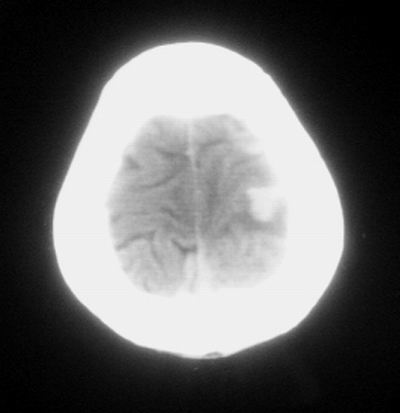

患者,男,30岁,右侧面部麻木,右上肢活动受限27小时。pe:神清、呼吸平稳,口角左歪,右上肢活动受限,右手掌握力消失,右侧躯体痛觉减退。

第一次颅脑ct扫描:左侧额顶叶血肿。